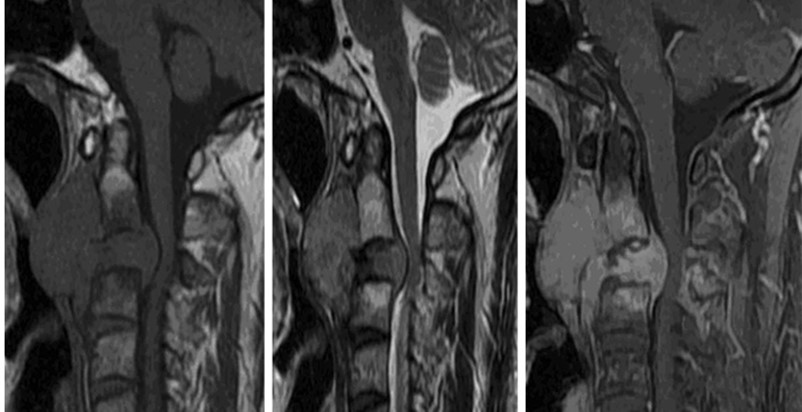

• MRIにて、腫瘤はT1WI、T2WIにて筋肉よりやや高い信号で、内部に液状のT2WI高信号を認めるが、その他の信号は比較的均一で、内部を椎骨動脈が走行する。ヘモジデリン沈着や石灰化を疑う低信号域は見られない。

• T1WI、T2WI、Gd-T1WI